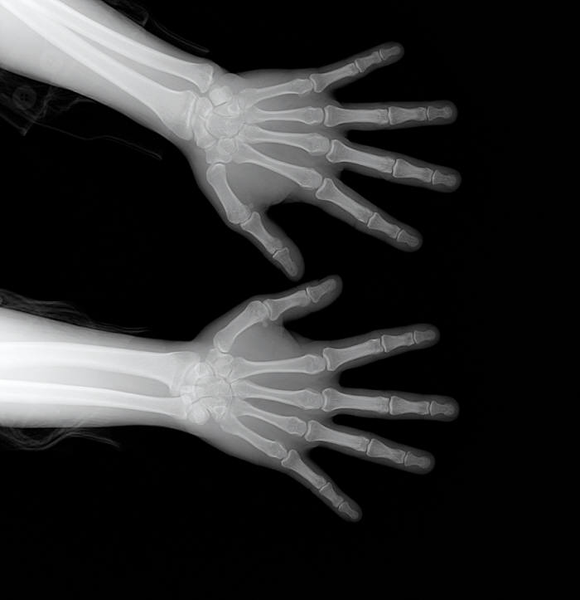

X-Ray

X-RAY는 방사선의 일종으로 지방, 근육, 천, 종이같이 밀도가 낮은 것은 수월하게 통과하지만, 밀도가 높은 뼈, 금속 같은 물질은 잘 통과할 수 없음

X-Ray 특성

- 뼈 : 하얀색

- 근육 및 지방 : 연한 회색

- 공기 : 검은색

몸을 통과한 전자기파에 따라 다르게 나오는 명암